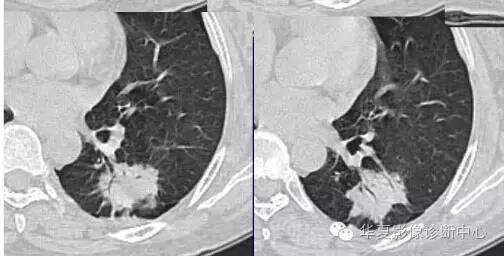

这一例是否GGO成分几乎没有

基本是实性的

那就按实性的分析

胸膜凹陷,分叶征

大家仔细看看这个中央不强化的腔内壁

你会发现内壁强化明显,边界清楚

一般这是炎性的脓腔,内层是肉芽肿,明显强化,分界清楚

癌肿的坏死一般是缺血性的,是肿瘤生长速度过快,中央带的血管受挤压,中央供血不足坏死的,一般边界模糊

内有内层强化,不会这么清楚

这是两者坏死的差异

内带强化带,边界清楚

但是这个其实整体看起来不是分叶征

只是一个一个的凸起